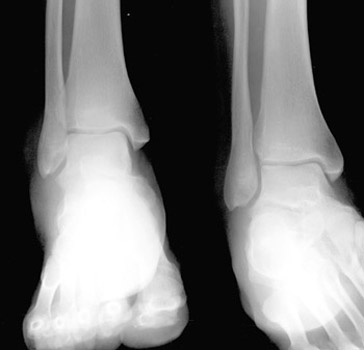

• Soft tissue swelling is usually present on the AP view as well, but there may be no acute fracture.

AP and Mortise views